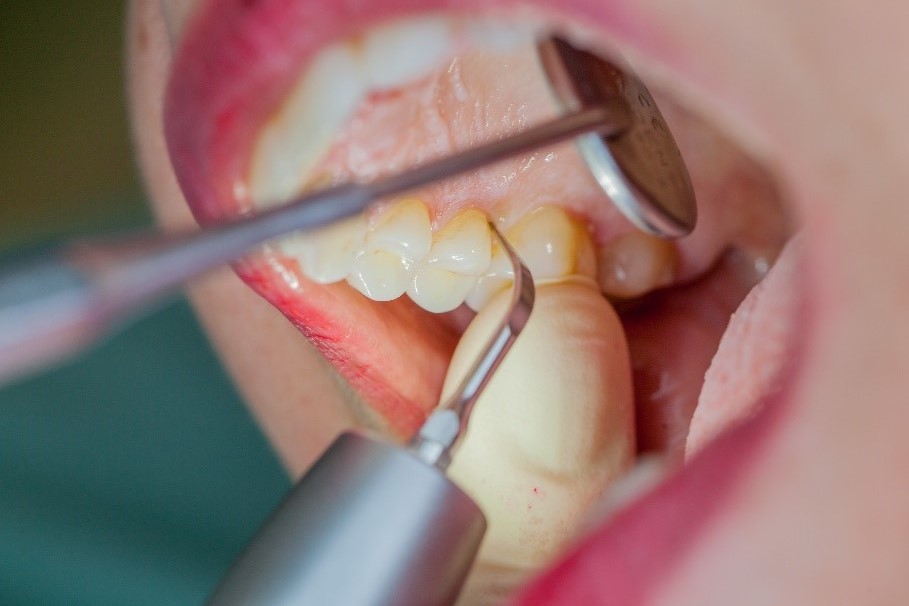

In the periodontal aftercare subsequent to implantation, soft (biofilm) and hard coatings are regularly professionally and mechanically removed.[16, 17] In the subgingival and supragingival areas, ultrasonic devices are generally used for this (Fig. 4), in combination with manual instruments where necessary. Alternatively, subgingival air polishing can be used in combination with periodontal attachments and powders.[18]